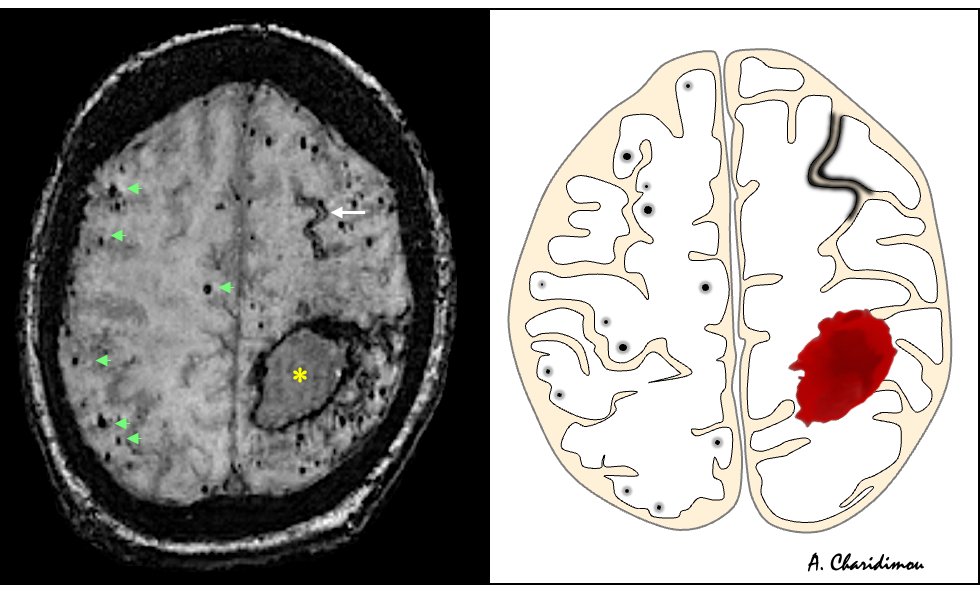

🩸🧠Hemorrhagic MRI manifestations of CAA (Cerebral Amyloid Angiopathy) 1) Lobar intracerebral hemorrhage 🩸 2) Lobar cerebral microbleeds ⚫️ 3) Cortical superficial siderosis 🎢 #neurotwitter #radres #NeuroTwitter #NeuroRad #Neurology #Neurosurgery #RadEd #stroke #Alzheimers

🩸🧠Hemorrhagic MRI manifestations of CAA

(Cerebral Amyloid Angiopathy)

1) Lobar intracerebral hemorrhage 🩸

2) Lobar cerebral microbleeds ⚫️

3) Cortical superficial siderosis 🎢